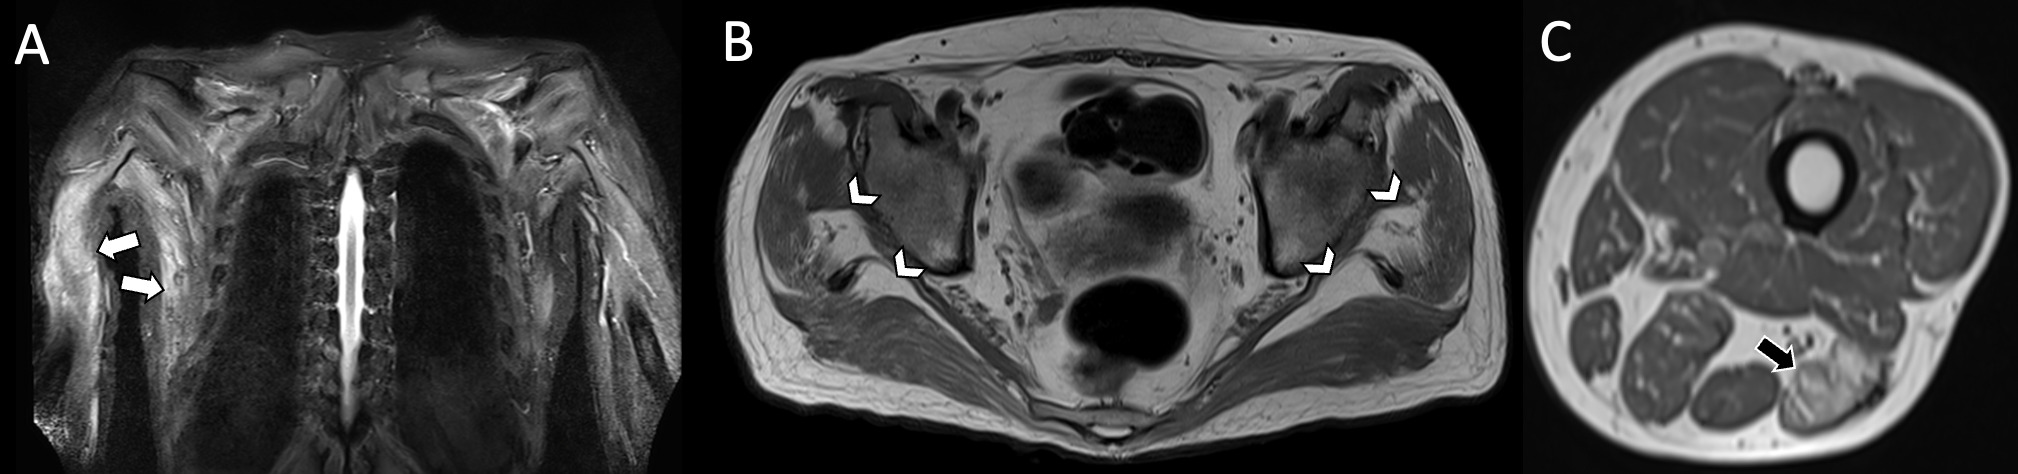

Complementary tests were conducted to determine the systemic involvement of the disease. Abdominal ultrasound revealed hepatomegaly. Solid neoplasms were ruled out via computed tomography (CT). Holter echocardiography results were negative for heart disease and kidney function with normal proteinuria values, and tumor and infectious markers showed negative results. Respiratory function tests showed a severe restrictive lung pattern. Shoulder and pelvic girdle Magnetic Resonance Imaging (MRI) revealed muscle edema and fatty atrophy in pelvic girdle muscles, along with significant muscle edema in the high shoulder girdle (Figure 2).

Figure 2. MRI without contrast. A) Coronal fat-saturated T2-weighted image of the shoulder girdle shows diffuse edema of the muscle groups, most evident in the right triceps and latissimus dorsi muscles. B) Axial T1-weighted image without fat saturation of the pelvic girdle shows atrophy and fat replacement of the muscle groups, most evident in the gluteus medius and maximus muscles on both sides. C) The lower sections also show atrophy and fatty replacement of the posterior muscular compartments of both thighs, most evident in the long head of the left biceps femoris.